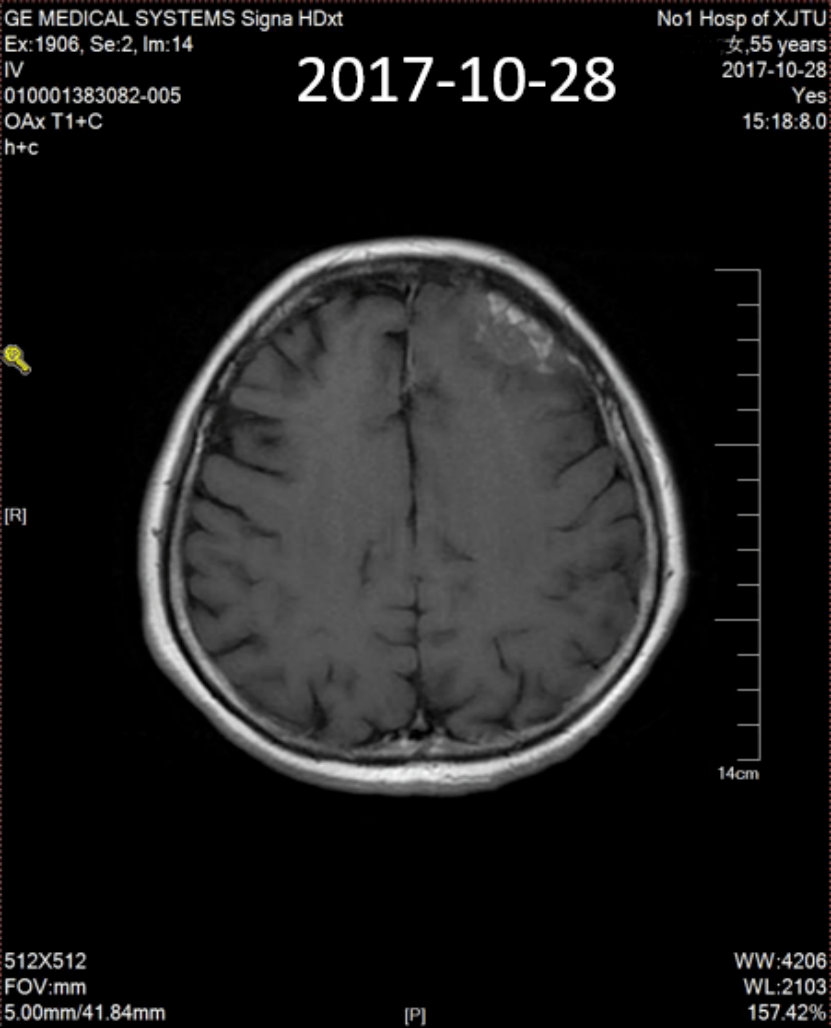

头颅CT(2017年10月28日)示:左额部颅板下不规则病灶,线状及环形强化,周围脑沟似见压迫征象,符合乳腺癌脑转移(图3)。

图3:头颅CT(2017年10月28日)